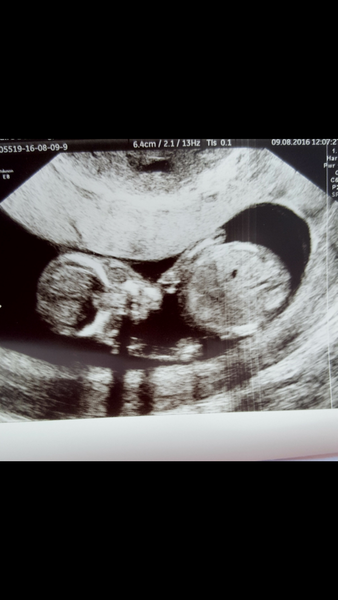

Ubercorn · 09/08/2016 15:10

12w scan went well. Baby is a lazy little toad! Was lying on his/her side, facing towards us but head tucked down and legs tucked up. Sonongrapher needed baby either on it's back or lying with it's back to us so she could get the measurements to date me. She tried pressing, she had me on the bed, off the bed, "can you roll side to side for a few seconds?", I had to raise up a little bit and then let me hips flop back onto the bed. And what did the baby do? Rolled over so we cheered..... and the little tinker kept going until it had done a full 360 degree turn and was back in its original position. Then it put its hands over its head as if to say "kindly bugger off, one is trying to have a sleep". So we had to start again with the rocking and on/off the bed.

My money is on it being a girl, this is exactly what DD was like at her scans.

Baby eventually cooperated and due date is now 19th Feb. That was DS2's due date, I had my 12w scan with him on 9th August and my 20w scan on 4th October. They've booked my 20w scan this time for 4th October Grin

Due in February 2017....thread 5!